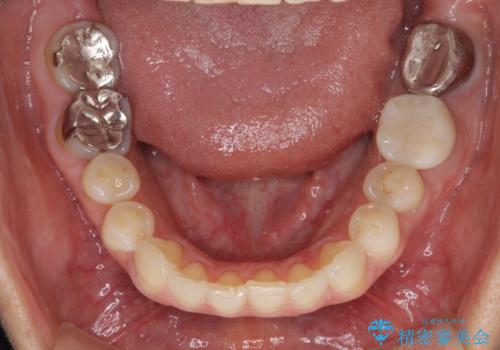

矯正治療後には、左下奥歯の症状がないことを確認し、セラミッククラウンにて補綴治療を行うこととしました。

根管治療を行う上で、ラバーダム防湿は処置の中で最も重要な要素です。

矯正治療後のレントゲン写真では、根尖部に認められた病変(骨の溶けていた像)は消失していることが分かりました。